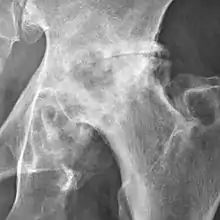

Severe (Tönnis grade 3) osteoarthritis of the hip.

Tönnis classification[9]

Grade Description

0No osteoarthritis signs

1Mild:

• increased osteosclerosis

• minor joint space narrowing (normal joint space is at least 2 mm at the superior acetabulum)[7]

• no or minor loss of head sphericity

2Moderate:

• small bone cyst

• moderate joint space narrowing

• moderate loss of head sphericity

3Severe:

• large bone cysts

• severe joint space narrowing, or joint space obliteration

• severe deformity of the head